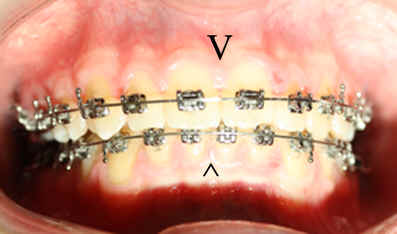

Malpositioned Premolar 13 year-old Caucasian boy

Pre-op 2009/04/18